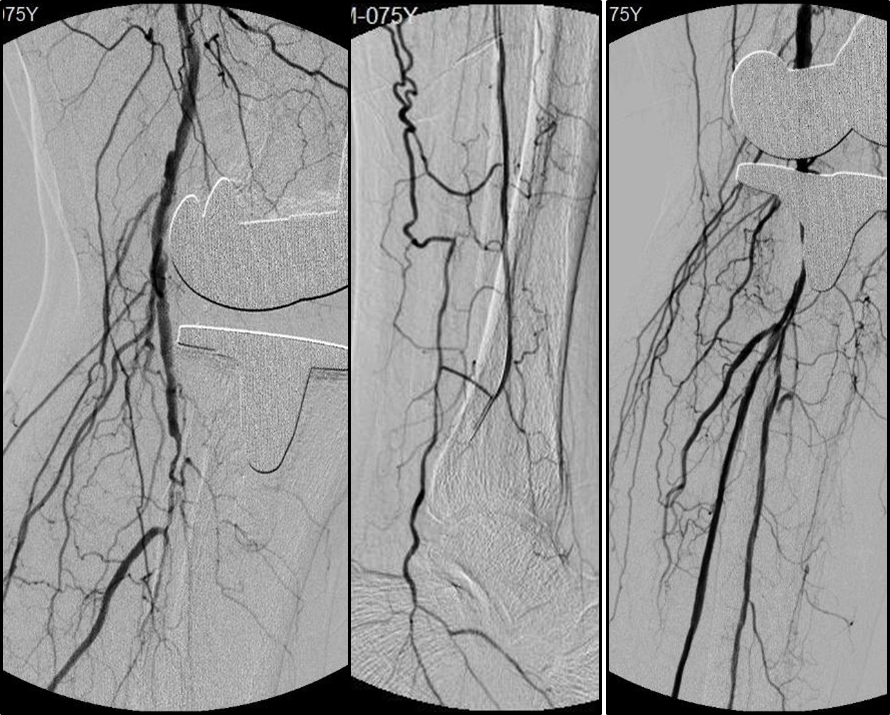

针对BTK病变,可采用多种腔内技术:

顺行技术

Knuckle/ADR(Antegrade Dissection and Re-entry)

AFR(Antegrade Fenestration and Re-entry)

BAM(Balloon-Assisted Microdissection)

BASE(Balloon-Assisted Subintimal Entry)

Stick-and-go

Stick-and-swap

Scratch-and-go

逆行技术

Trans-luminal

From no-target artery

Through pedal arch or ACA/PCA

To distal cap of CTO in target artery

Transcutaneous

Surgery exposure

Puncture

在操作中需遵循两大核心原则:

ALARA原则:在保证疗效的前提下,尽可能降低辐射剂量和造影剂用量。

区域化操作策略:

平直区域:可快速通过(真腔或内膜下);

关键区域(如CTO开口、出口、BTA区域):必须谨慎操作,避免穿孔等并发症。